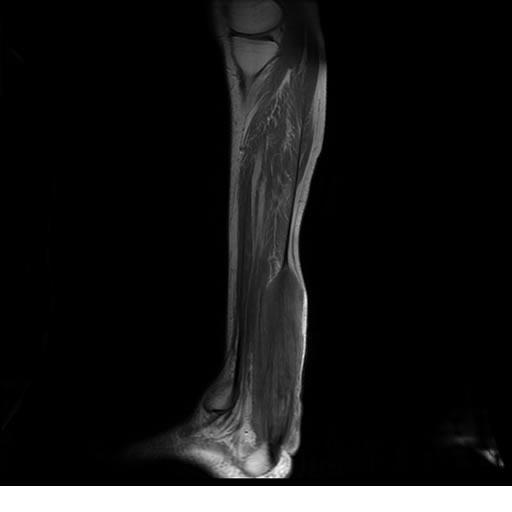

Se realiza estudio de MRI de pierna izquierda, utilizando secuencias Spin Echo y GRE en diferentes planos, se realiza angio MRI en fase arterial y venosa de pierna izquierda

El estudio demuestra masa a nivel de los músculos gemelos, más evidente en secuencia con pulso de saturación de grasa, en el estudio de angio resonancia de pierna la fase arterial no muestra ninguna anormalidad, en la fase venosa se observa acumulo del medio de contraste a este nivel.

Se concluye que se observa una masa de tejido muscular sumamente vascularizada compatible con un hemangioarcoma.